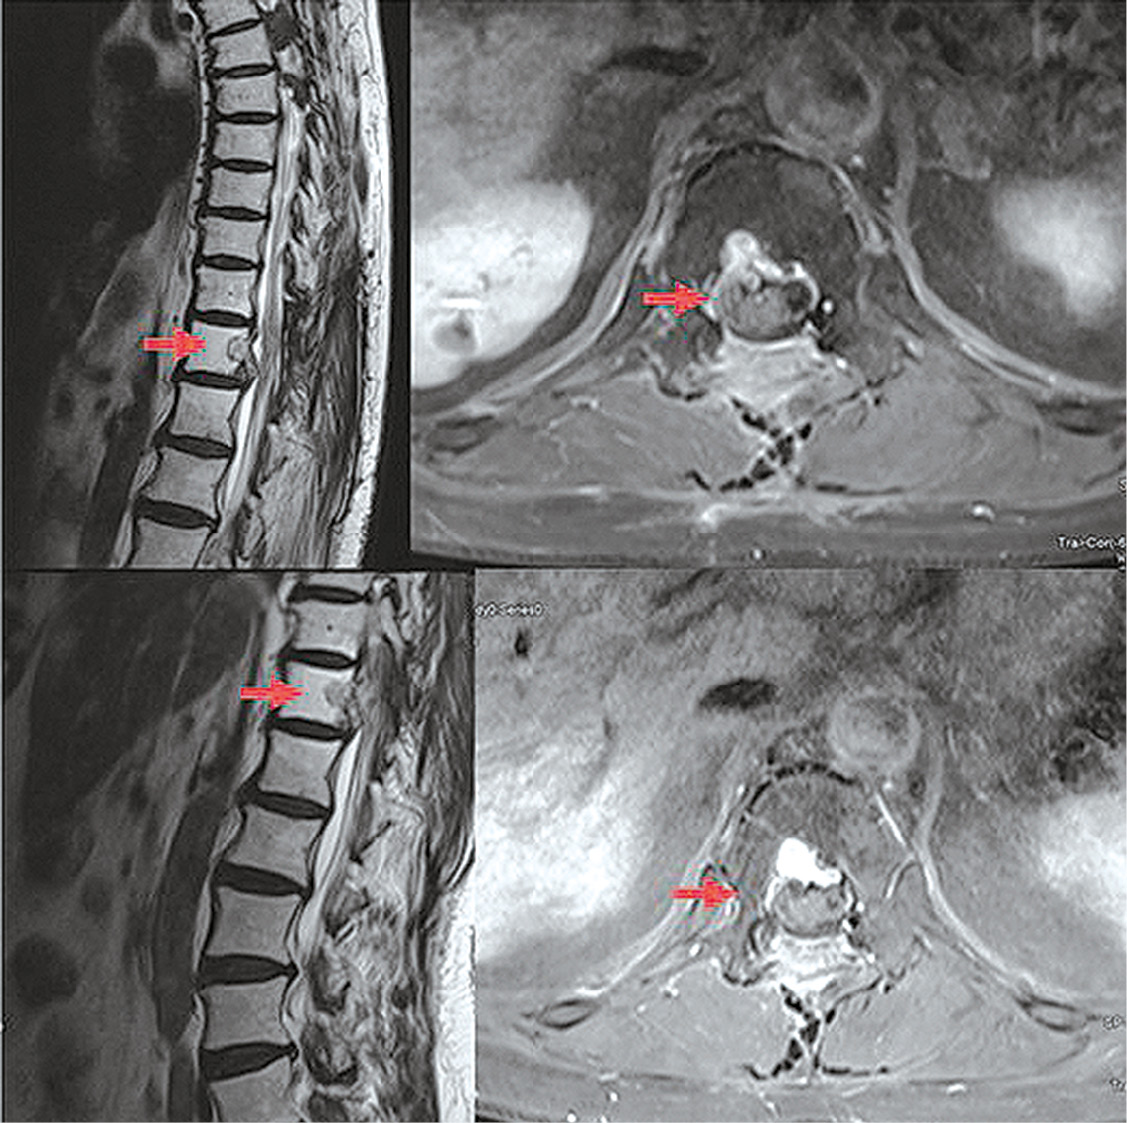

Patient T., female, 75 years old; a history of meningothelial arachnoidal endothelioma resection at the Th6–Th7 level on July 13, 1988. In 2019, the patient began experiencing weakness and pain in the right leg, which increased in severity. On December 22, 2020, the patient was admitted to the Karpovich Krasnoyarsk Interdistrict Clinical Emergency Hospital with the diagnosis of moderate coronavirus disease. Computed tomography (CT) of the chest revealed a lytic lesion of the T12 vertebral body. After recovering from COVID-19-associated pneumonia, the patient was discharged with suspected local tumor recurrence. Magnetic resonance imaging (MRI) of the spine with intravenous contrast revealed an intradural extramedullary tumor of the thoracic spine at the Th12 level, measuring 1.7×2.3×2.3 cm and extending to the intervertebral foramen. Other MRI findings included vertebral destruction and spinal cord deformation and compression (Fig. 1). On November 15, 2022, neurosurgeons at the N.S. Karpovich Krasnoyarsk Interdistrict Clinical Emergency Hospital performed Th11–12 laminectomy and resection of an extra-intradural extramedullary tumor of the anterior dural sac. The tumor extended into the dura mater of the conus medullaris. The patient was diagnosed with low-grade (G1) CHS based on the surgical specimen immunohistochemistry. The specimen was further examined in the anatomic pathology department of the Blokhin National Medical Research Center of Oncology, and the diagnosis was confirmed. A post-operative contrast-enhanced MRI revealed no signs of tumor in the Th12 vertebra and no paramagnetic contrast uptake areas (Fig. 1).

Fig. 1. MRI of the spine, T1 mode. The top picture is before surgery (tumor in Th12). The bottom photo is after the operation (the formation is not visualized).

Рис. 1. МРТ позвоночника, режим T1. Верхний рисунок — до операции (опухоль в Th12). Нижнее фото — после операции (образование не визуализируется).